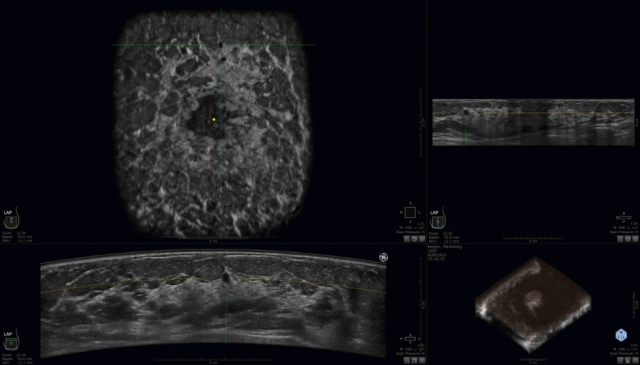

自动乳腺容积超声成像(Automated

Breast Ultra

Sound

ABUS)是一种新型高分辨率乳腺三维超声成像技术,具有能够获得全乳腺解剖结构成像(包括横切面、矢状面和冠状面)、探头自动扫描以及左右乳腺同屏对比等优点,也可从三维角度、多层面观察乳腺的内部结构,改变了手持超声相对依赖操作者经验、成像面积小和没有冠状面图像等缺点。与乳腺X线摄影技术比较,自动乳腺容积超声没有辐射性且对于致密型乳腺尤为有益。

摆脱了传统手持超声对操作人员扫查手法的依赖,ABUS可实施标准化操作、标准化成像、标准化报告,自动生成全容积乳腺超声图像。

一次采集获得6个标准切面,采集全乳信息,可以提供手动超声不能提供的冠状面信息和容积成像,更方便临床定位和直观地提供病灶信息。